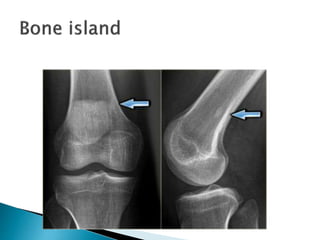

 Benign lesionconsisting of well-differentiated mature bone tissue within the medullary cavity.  Also known as enostosis  The shape is usually round or oval.  Frequently encountered as a coincidental finding and can be found in any bone.  Occasionally slowly enlargement can be seen.  Bone islands can be large at presentation.  Bone scan shows no high activity, opposed to low-grade intraosseous osteosarcoma

• 15.